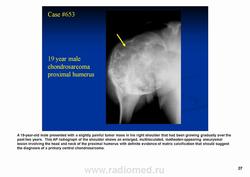

Хондросаркома — злокачественная опухоль, клетки которой продуцируют хрящ. Встречается относительно часто (составляет около 10% всех злокачественных опухолей костей). Обнаруживается в возрастной группе от 5 до 90 лет, в основном в среднем и пожилом возрасте — чаще между 40 и 60 годами (около 60% больных), с несколько большей частотой обнаруживается у мужчин. Выделяют по локализации — центральную (костномозговую) и периферическую (юкстакортикальную) формы, а также первичную и вторичную хондросаркомы – последняя развивается из предсуществующих доброкачественных опухолей, в основном из энхондром и остеохондром (особенно множественных). Вторичная хондросаркома встречается в более молодом возрасте (около 60% больных в возрасте 30–40 лет). Может поражаться любая кость хрящевого происхождения. Наиболее частая локализация (три четверти больных) — кости туловища (рёбра, грудина, таз) и верхние концы бедренной и плечевой костей; редко поражаются кости костей и стоп.

С диагностической точки зрения хондросаркомы подразделяют на хондросаркомы низкой (I), средней (II) и высокой (III) степени злокачественности. Почти 60–90% хондросарком относится к хондросаркомам низкой и средней степени злокачественности.

Рентгенологически выявляют в очаге деструкции участки обызвествления в виде крапчатости; кортикальный слой с признаками эрозии со стороны эндоста и истончения; размеры опухоли более 4 см; периостальная реакция слабо выражена или отсутствует; может наблюдаться деструкция кортикальной кости и наличие мягкотканного компонента; в длинных костях локализуется чаще в метафизах и диафизах; интенсивное внутрикостномозговое распространение.